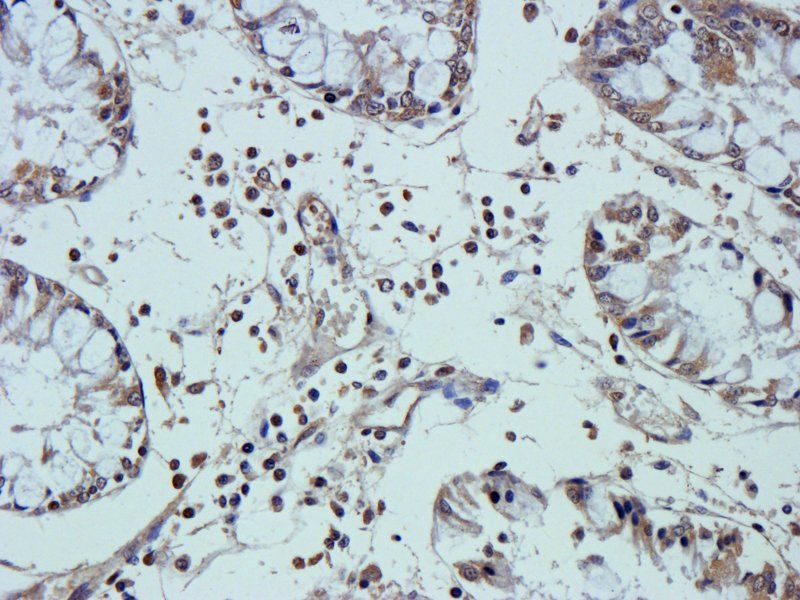

100 μg, 10 μg - Anti-Glucose Transporter GLUT1/SLC2A1 Antibody [orb259612]

FC, ICC, IF, IHC, IHC-Fr, WB

Human, Mouse, Rat

Rabbit

Polyclonal

Unconjugated